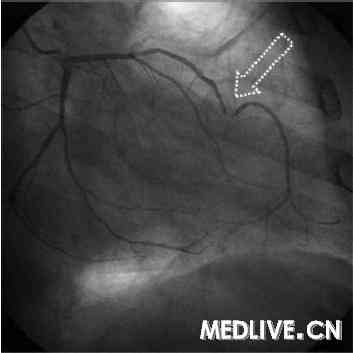

患者,男,63岁,有吸烟史,患有高脂血症,最近出现典型劳力型心绞痛(伴有超声心电图应激试验阳性结果显示心尖缺血)后被转诊(到本院)进行冠状动脉造影。冠状动脉造影显示一种奇怪的左前降支(LAD)中部变形(伴有一个左心室尖部动脉瘤)(图1)。因此,我们决定实施一次MRI检查。

图1. 冠状动脉造影显示LAD动脉中部远端一处极度致密的狭窄(箭),

伴有该动脉不常见的变形。